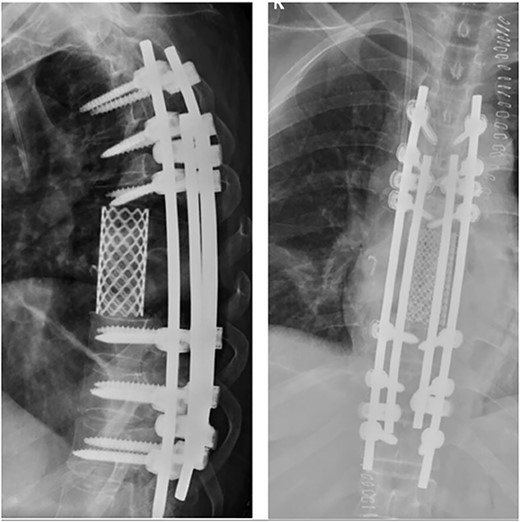

Posterior spinal instrumentation was performed with pedicle screws, three levels above and below T7. During the last pedicle coronal passing of the Tomita saw, a complete loss of abdominal and lower limbs potentials happened. Mean blood pressure above 85 mmHg was monitored, patient’s temperature was raised, and NASCIS protocol for acute spinal cord injury was initiated. After coronal cuts of the pedicles were completed, cephalic axial cut at T6 vertebral body and caudal cut at T8T9 intervertebral disk were performed. The piece was then removed en bloc (Fig. 4). Reconstruction with anterior mesh packed with allograft was performed. Posterior reconstruction was completed with double bar on each side for a more stable construct, with proximal tibia autograft covering the laminae for graft support and protection of the posterior spinal cord from muscular pressure (Fig. 5).

Total en bloc vertebrectomy of T7 and T8 and partial vertebrectomy of caudal T6.

Anterior reconstruction with mesh and posterior reconstruction with T4T5T6, T9T10T11 screws, and double bar.

Two years after surgery, adequate clinical recovery continues, with a high-degree satisfaction, persisting mild lumbar pain, and a slight weakness in the right foot. Pertinent X-rays show normal position of the implants with no implant loosening (Fig. 10).

X-rays showing normal position of the implants with no signs of loosening.